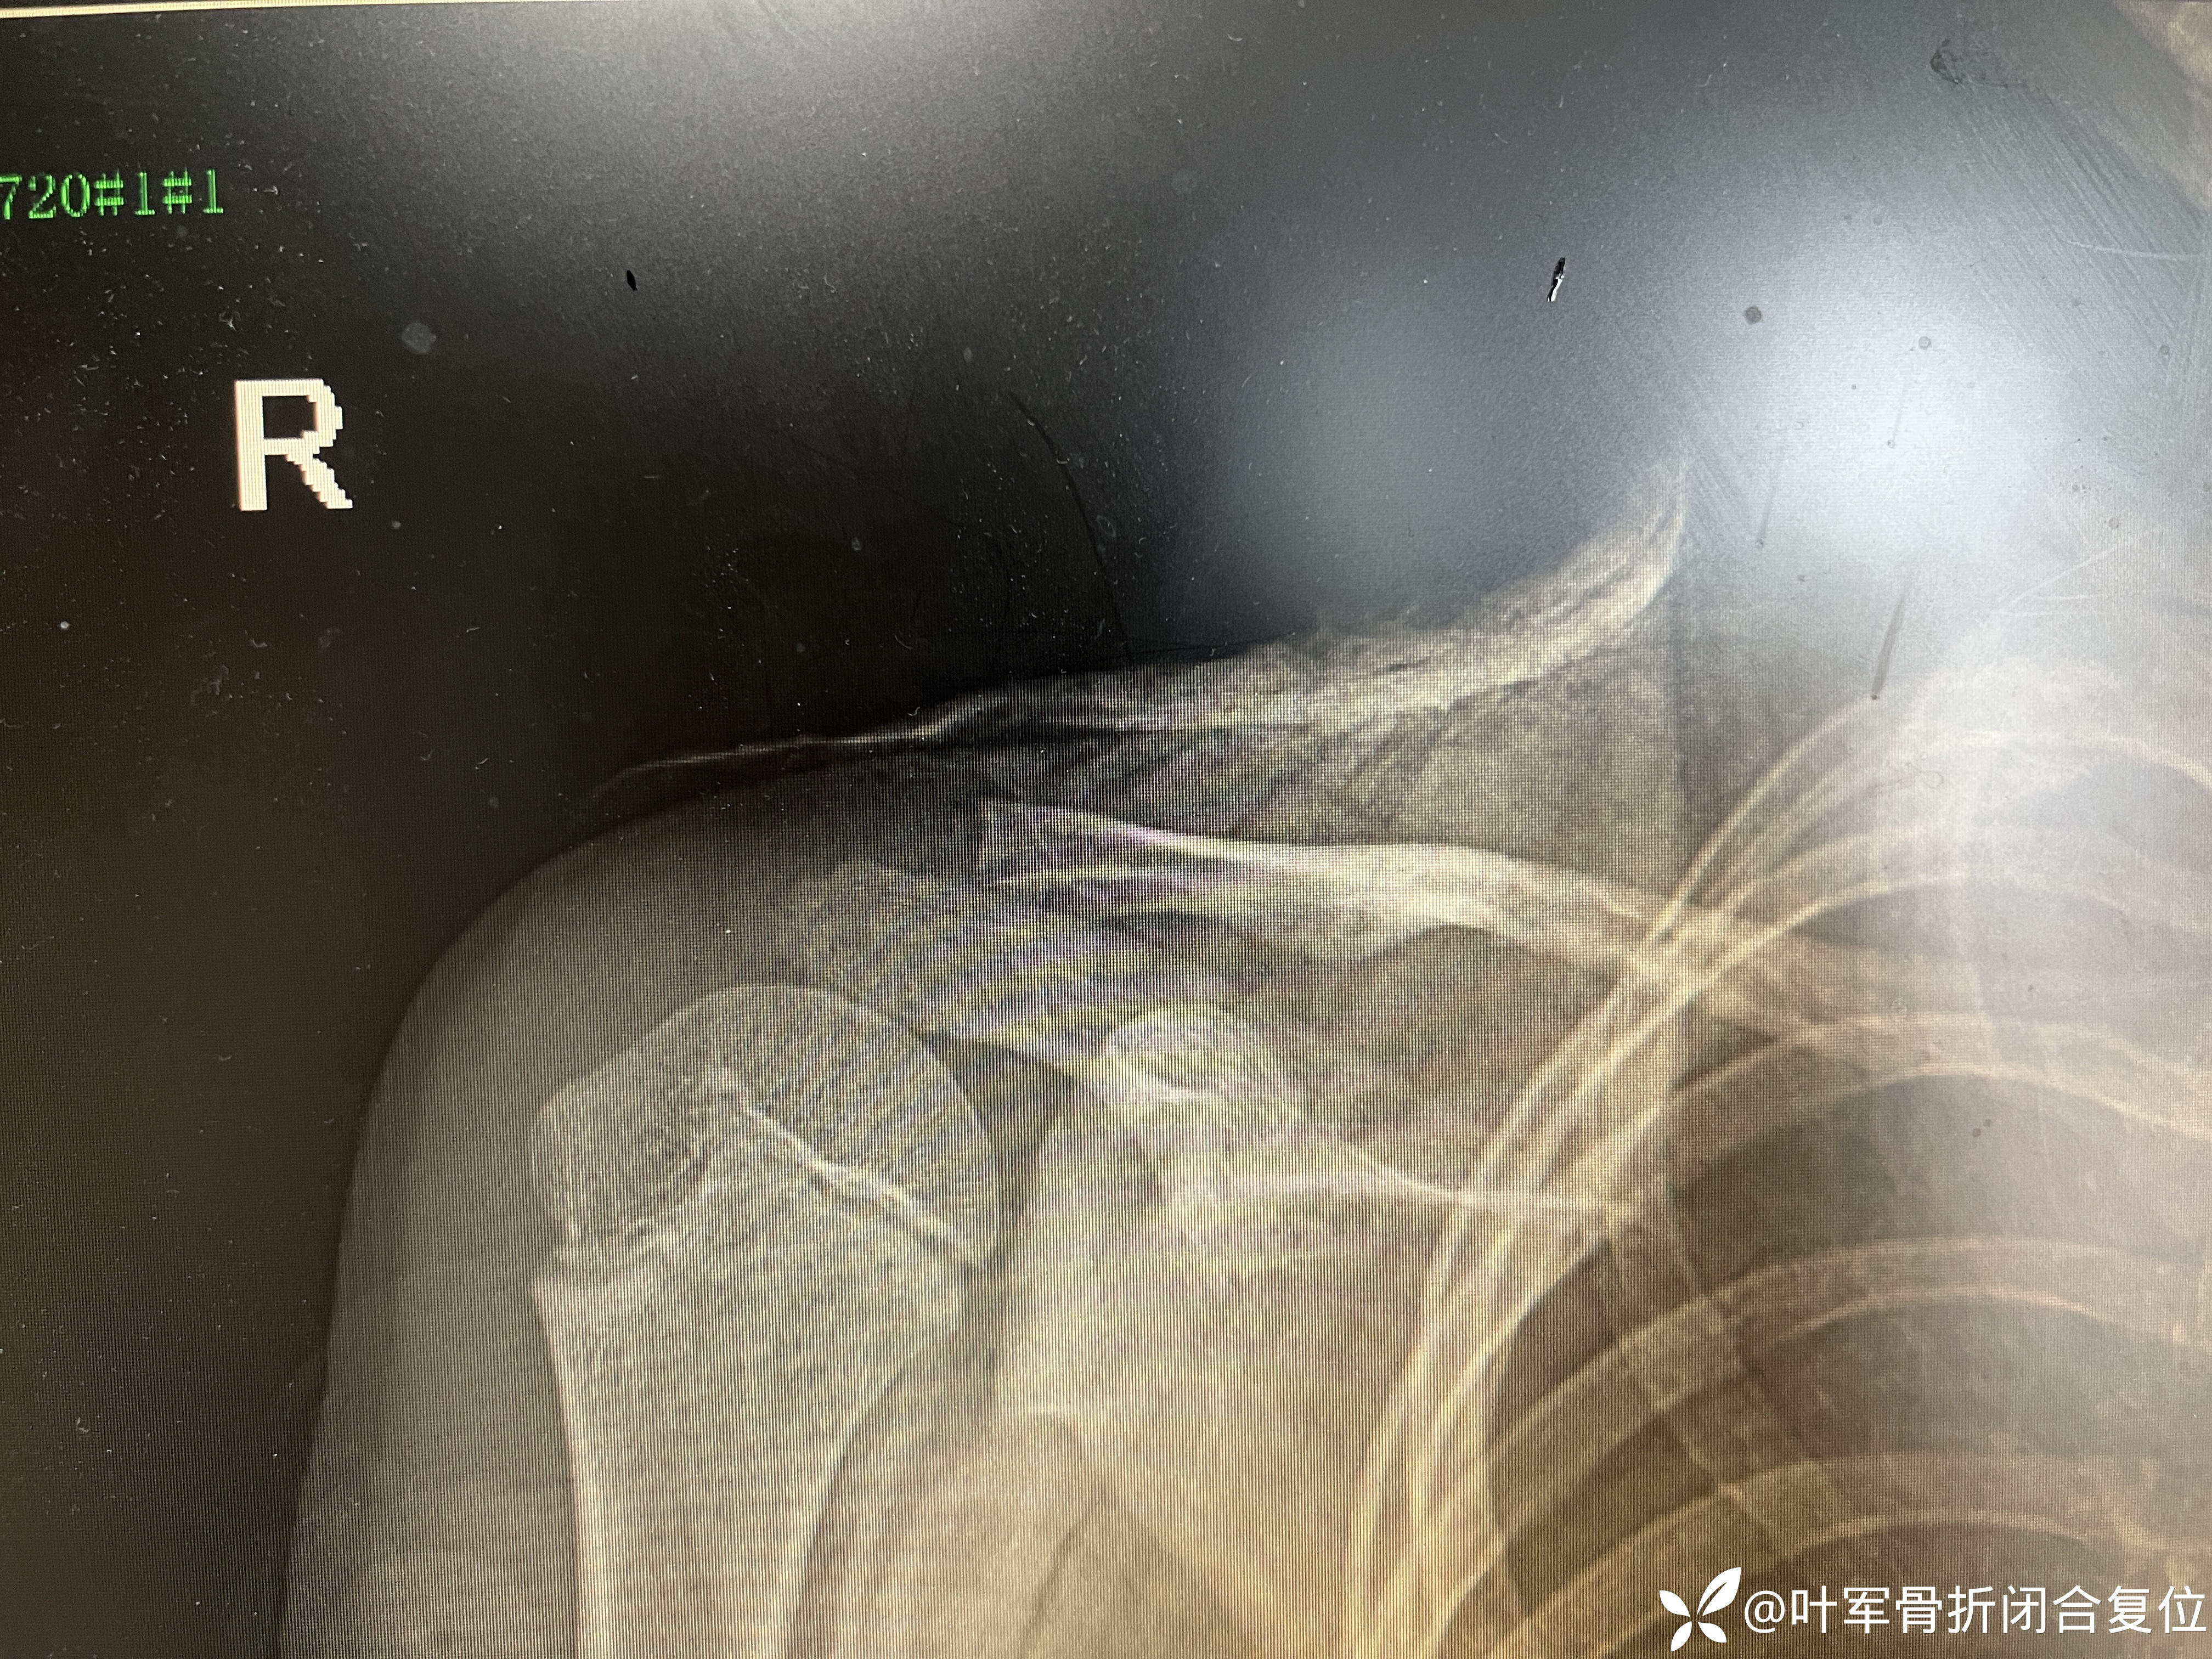

术后复查 患儿第二天高兴离院

复位情况